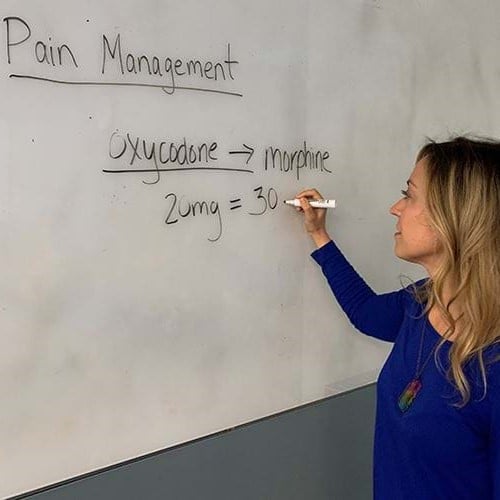

Hospice and Palliative Medicine →

The Hospice and Palliative Medicine fellowship is dedicated to training generations of palliative care experts to provide compassionate, evidence-based, interdisciplinary care for seriously ill patients and their families to improve quality of life and reduce physical, emotional and spiritual suffering. We mentor fellows as servant-leaders committed to teaching, program growth, quality improvement and research to grow the field of palliative care locally, regionally and nationally.